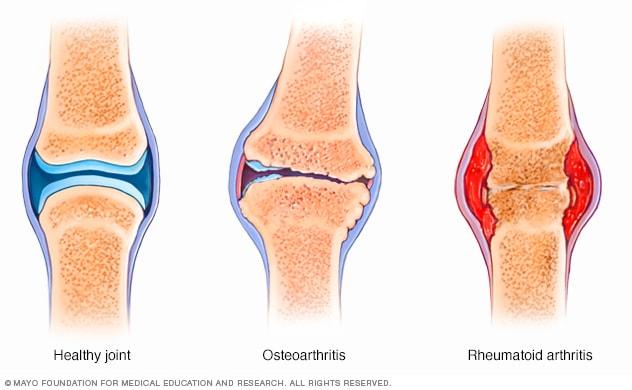

La artritis reumatoide es una enfermedad crónica que afecta principalmente a las articulaciones, causando dolor e inflamación en quienes la padecen. En el caso de los adultos mayores, la necesidad de intervenciones quirúrgicas para tratar esta condición es cada vez más frecuente. En Medellín, la capital de la moda en Colombia, se llevan a cabo múltiples procedimientos quirúrgicos para combatir los efectos de la artritis reumatoide en esta población vulnerable. En este artículo, exploraremos las diversas intervenciones quirúrgicas disponibles para adultos mayores con artritis reumatoide en Medellín, destacando los avances y opciones de tratamiento disponibles en la ciudad.

En esta reseña, se analizarán los resultados y pronósticos de intervenciones quirúrgicas realizadas en Medellín para tratar la artritis reumatoide en adultos mayores. La artritis reumatoide es una enfermedad crónica que afecta las articulaciones y puede causar dolor e inflamación, especialmente en personas de edad avanzada.